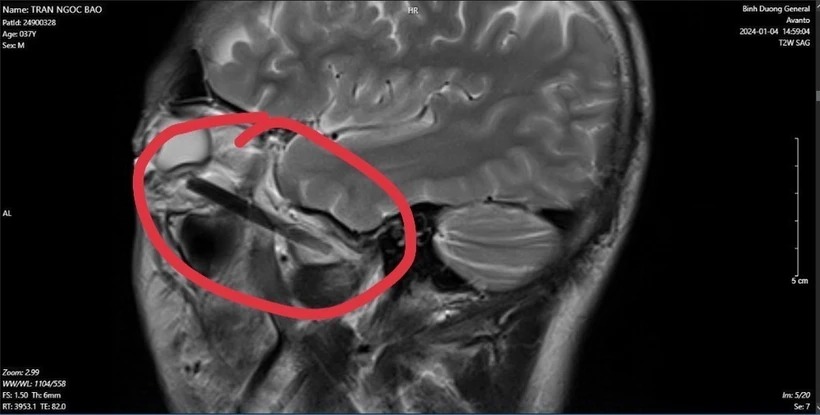

Hình ảnh dị vật trong mắt người đàn ông ở tỉnh Bình Dương. (Ảnh: TTXVN phát)

Các bác sỹ phát hiện một phần chiếc đũa dài khoảng 6cm, nằm sâu trong hốc mắt người đàn ông này.

Sau khi phẫu thật, các bác sỹ đã lấy được dị vật trong hốc mắt của người bệnh là đầu đũa gỗ bị gãy với chiều dài gần 6cm.